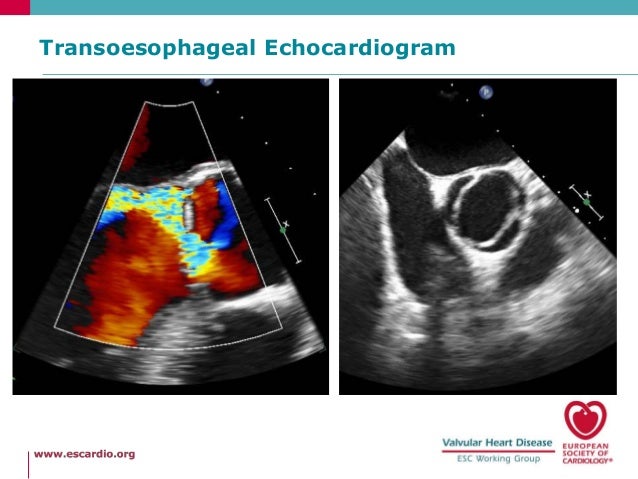

The development and timing of aortic valve prolapse (AoVP) and aortic regurgitation (AR) was studied by two-dimensional echocardiography in 99 consecutive patients with supracristal ventricular septal defect (VSD). Thirty patients (30%) had aortic valve prolapse (VSD + AoVP group), and 31 patients (31%) had AoVP with AR (VSD + AoVP + AR group). In the VSD + AoVP group, AoVP was detected first by echocardiography at the age of 6.8 +/- 4.2 years (mean +/- SD). In the VSD + AoVP + AR group, the interval from detection of AoVP to the appearance of AR was 3.4 +/- 2.0 years. The configuration of the prolapsed aortic valve was echocardiographically classified into two types: tear-drop type (small) prolapse and box type (large) prolapse. The frequency of tear-drop type prolapse was not significantly different between VSD + AoVP and VSD + AoVP + AR groups (43% versus 32%, respectively), indicating that even minor AoVP can result in AR. Four infants (4%) had AoVP at the ages of 1, 5, 7, and 11 months, respectively. All infants had tear-drop type prolapse. Two infants developed AR by colour flow mapping at the ages of 3 and 11 months, and the interval from prolapse to AR was only 2 and 4 months, respectively.

Aortic valce involvement can develop under the age of 1 year in supracristal VSD. Regular evaluation by two-dimensional echocardiography with colour flow mapping is important in the follow-up of children with supracristal VSD.